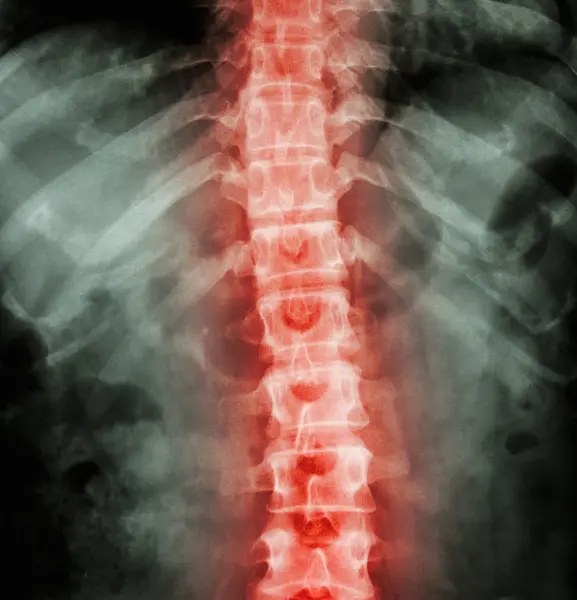

If it’s your first time seeking thoracic pain treatment in Dyer, IN, rest assured that you’re in capable hands. We also evaluate related issues, such as neck pain, to ensure a comprehensive treatment plan. Our process begins with a thorough review of your medical history, followed by a physical examination to pinpoint the source of your thoracic back pain. To gain more insights, we may use advanced imaging techniques like X-rays or MRIs. Once we confirm the cause, our team develops a customized treatment plan tailored to your needs, focusing on providing relief and improving your overall health.